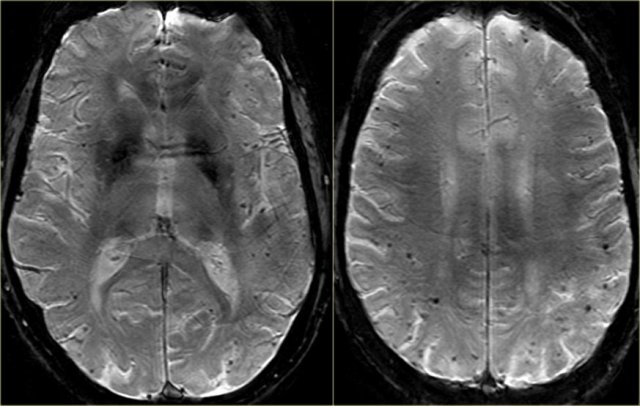

Fazekas scale for WM lesions

On MR, white matter hyperintensities (WMH) and lacunes - both of which are frequently observed in the elderly - are generally viewed as evidence of small vessel disease.

The Fazekas-scale provides an overall impression of the presence of WMH in the entire brain.

It is best scored on transverse FLAIR or T2-weighted images.

Score:

- Fazekas 0: None or a single punctate WMH lesion

- Fazekas 1: Multiple punctate lesions

- Fazekas 2: Beginning confluency of lesions (bridging)

- Fazekas 3: Large confluent lesions

Fazekas 1 is considered normal in the elderly.

Fazekas 2 and 3 are pathologic, but may be seen in normally functioning individuals.

They are however, at high risk for disability.

In 600 normally functioning elderly people the Fazekas score predicted disability within one year (table).

In the Fazekas 3 group 25% was disabled within one year (10).

Three year follow-up shows that severe white matter changes independently and strongly predict rapid global functional decline (17).